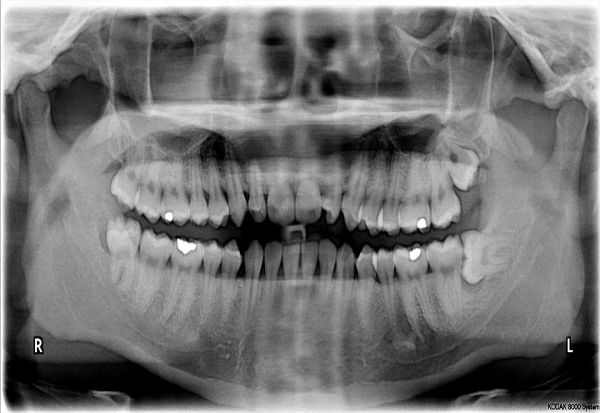

zabi

Фото: Wikimedia Commons